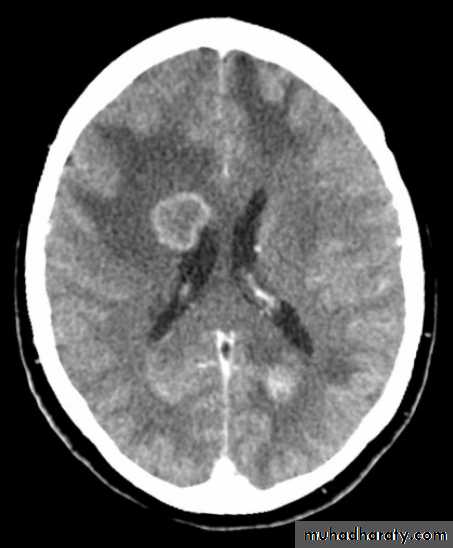

Secondary metastasis

Old age group above 50 Y , any lesion within the cerebellar hemisphere it is secondary metastasis unless proven otherwise F. from breast CA M. from bronchogenic CA .

Appear as nodular single or multiple lesion hypo dense or hyper dense .

Surrounded by per focal edema

Enhanced as solid or ring pattern of enhancement .